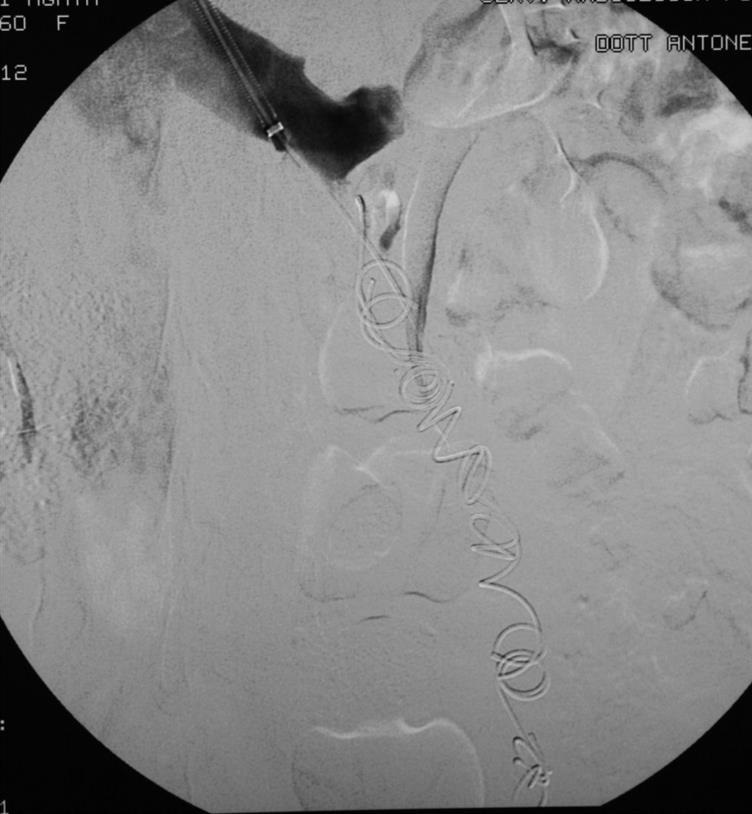

Embolization of Ovarian Vein Varices

Embolization 材料包括

• Coils

• Sclerosing agent

• Glue

• Combination

1: Coïls only 2: Coïls + Foam 3: Coïls + Onyx

No. Coil 7.2 coils (2-21), 4 coils (1-15), 4 coils (2-10)

Average time procedure > 60 min < 45 min 60 min

Transitory pelvic pain (< 48 h): 5% 5% 2%

Transitory variation of temperature (38°C): yes yes -

Pain during the procedure 1 % 12 % (spasm and foam) 100 %(DMSO)

Bad Breath (Smell of garbit during 2 days): - - yes

migrating coils (without consequence) 2 1

pulmonary embolismce): (without consequence) 1 1

vision trouble (foam)q   1

Recurrence of SCP and/or SCVI(follow up) 8 % at 9 years 3 % at 5 years too short

cost the same the same more expensive